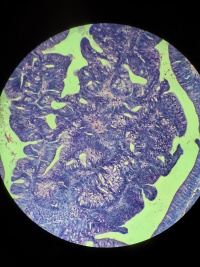

直乙交界肿物活检

不规则隆起性病变,菜花状,表面绒毛状颗粒,环周2/3,局部坏死,质脆,易出血。

直肠占位活检

灰白色小组织,易碎

腺癌,提高切片脱水、染色质量

肠镜下看上去不太妙。

标本处理不是很理想。

脱蜡不彻底